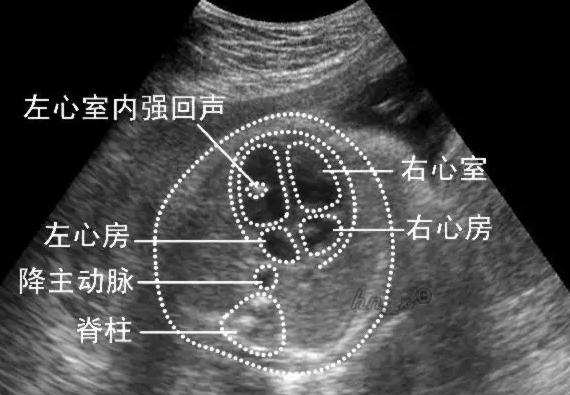

胎宝宝的左心室出现强光点到底严重不严重呢?首先我们需要看看什么情况会出现B超检查是传回强光点。其实这个强光点也被称之为“强回声点”,是胎儿心室内点状强回声是一个声像图表现而不是一种心脏畸形,更不是一种心脏异常诊断。以前的B超是看不到这种强光点的,随着科学技术的发展,如今的B超大夫可以在B超检查时看到。

以前B超检查受机器因素左心室强光点根本不可能看到,现在医院B超机器都先进了,以前看不到的能看见了,结果让很多准妈妈非常担心。其实胎儿心室内点状强回声是一个声像图表现而不是一种心脏畸形,更不是一种心脏异常诊断。但由于心脏超声常能看到,中期妊娠声像图上现实心室内强回声点得发生率约为2.1%-5%,也有报道在0.5%-20%。

心内强回声点一般不易与其他心脏疾病相混淆,但有时可能与小型初起的心室肿瘤相似。然而声像图上肿瘤总是与室间隔或心室壁相连,随访超声肿瘤会逐渐增大,而强回声会逐渐减小或消失。

临床上经常可以见到胎宝宝超声的时候发现有强回声光点儿的情况,如果强回声光点儿仅仅出现在左心室,并且只有一枚,那么这样的情况通常是没有什么临床意义的,也就是说没事儿的。如果右心室里面有数枚,或者左右心室里面都有,那么就要做进一步的检查了。

大部分强回声点随孕周增加而缩小,回声强度也逐渐减弱。到足月妊娠几乎完全消失,少数则可一直存在,直至分娩,甚至产后超声仍能观察到。对于大部分胎儿而言,心室内强回声点可能无重要的临床意义。单纯光点5mm,一般是钙化现象,可以说这个强光点基本上可以说99.%没问题的。在监测B超中出现强光点的案例中,出现染色体异常率为6.1%,绝大部分的宝宝在后期时逐渐散掉。不用担心,建议做好孕期的各项检查,面对这种医学专业问题,孕妈妈们就去寻求专业的医院来帮忙分析和给出靠谱的建议。